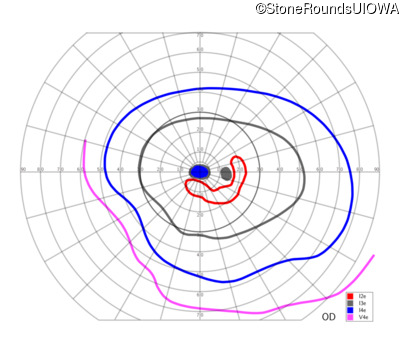

This 52 year old man had normal vision until his mid 30's when he began to have trouble distinguishing colors. the issuing 10 years he had a gradual loss of visual acuity accompanied by increasing photophobia.

| Age at visit: 55 years |

| Age at visit: 58 years |

| Age at visit: 61 years |

| Age at visit: 64 years |